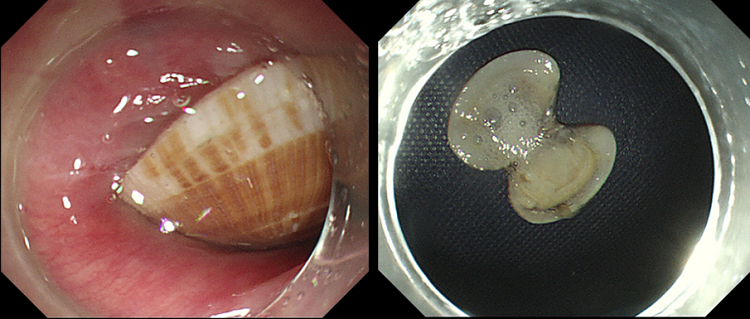

多科室協(xié)同下,林芬副主任醫(yī)師執(zhí)鏡操作,當(dāng)胃鏡進(jìn)入食道,只見(jiàn)一個(gè)花蛤嵌頓于食道上段。手術(shù)過(guò)程比想象得更加困難,稍有不慎邊緣銳利的花蛤殼就可能會(huì)劃破脆弱的食道,造成食道出血、穿孔。林芬副主任醫(yī)師小心翼翼用異物鉗鉗持花蛤的一端,通過(guò)異物鉗調(diào)整花蛤方向后,快速、精準(zhǔn)的將花蛤殼取出。僅用時(shí)大約2分鐘,最終卡在張大媽食管處、長(zhǎng)達(dá)2.3厘米邊緣鋒利的完整花蛤被取出來(lái)了!林芬副主任醫(yī)師再次進(jìn)鏡觀察,手術(shù)過(guò)程順利,未造成食道損傷。手術(shù)結(jié)束后,患者家屬對(duì)消化內(nèi)鏡中心、麻醉醫(yī)護(hù)團(tuán)隊(duì)的高超技術(shù)及勇于擔(dān)當(dāng)?shù)木裆畋砀屑ぁ?/span>